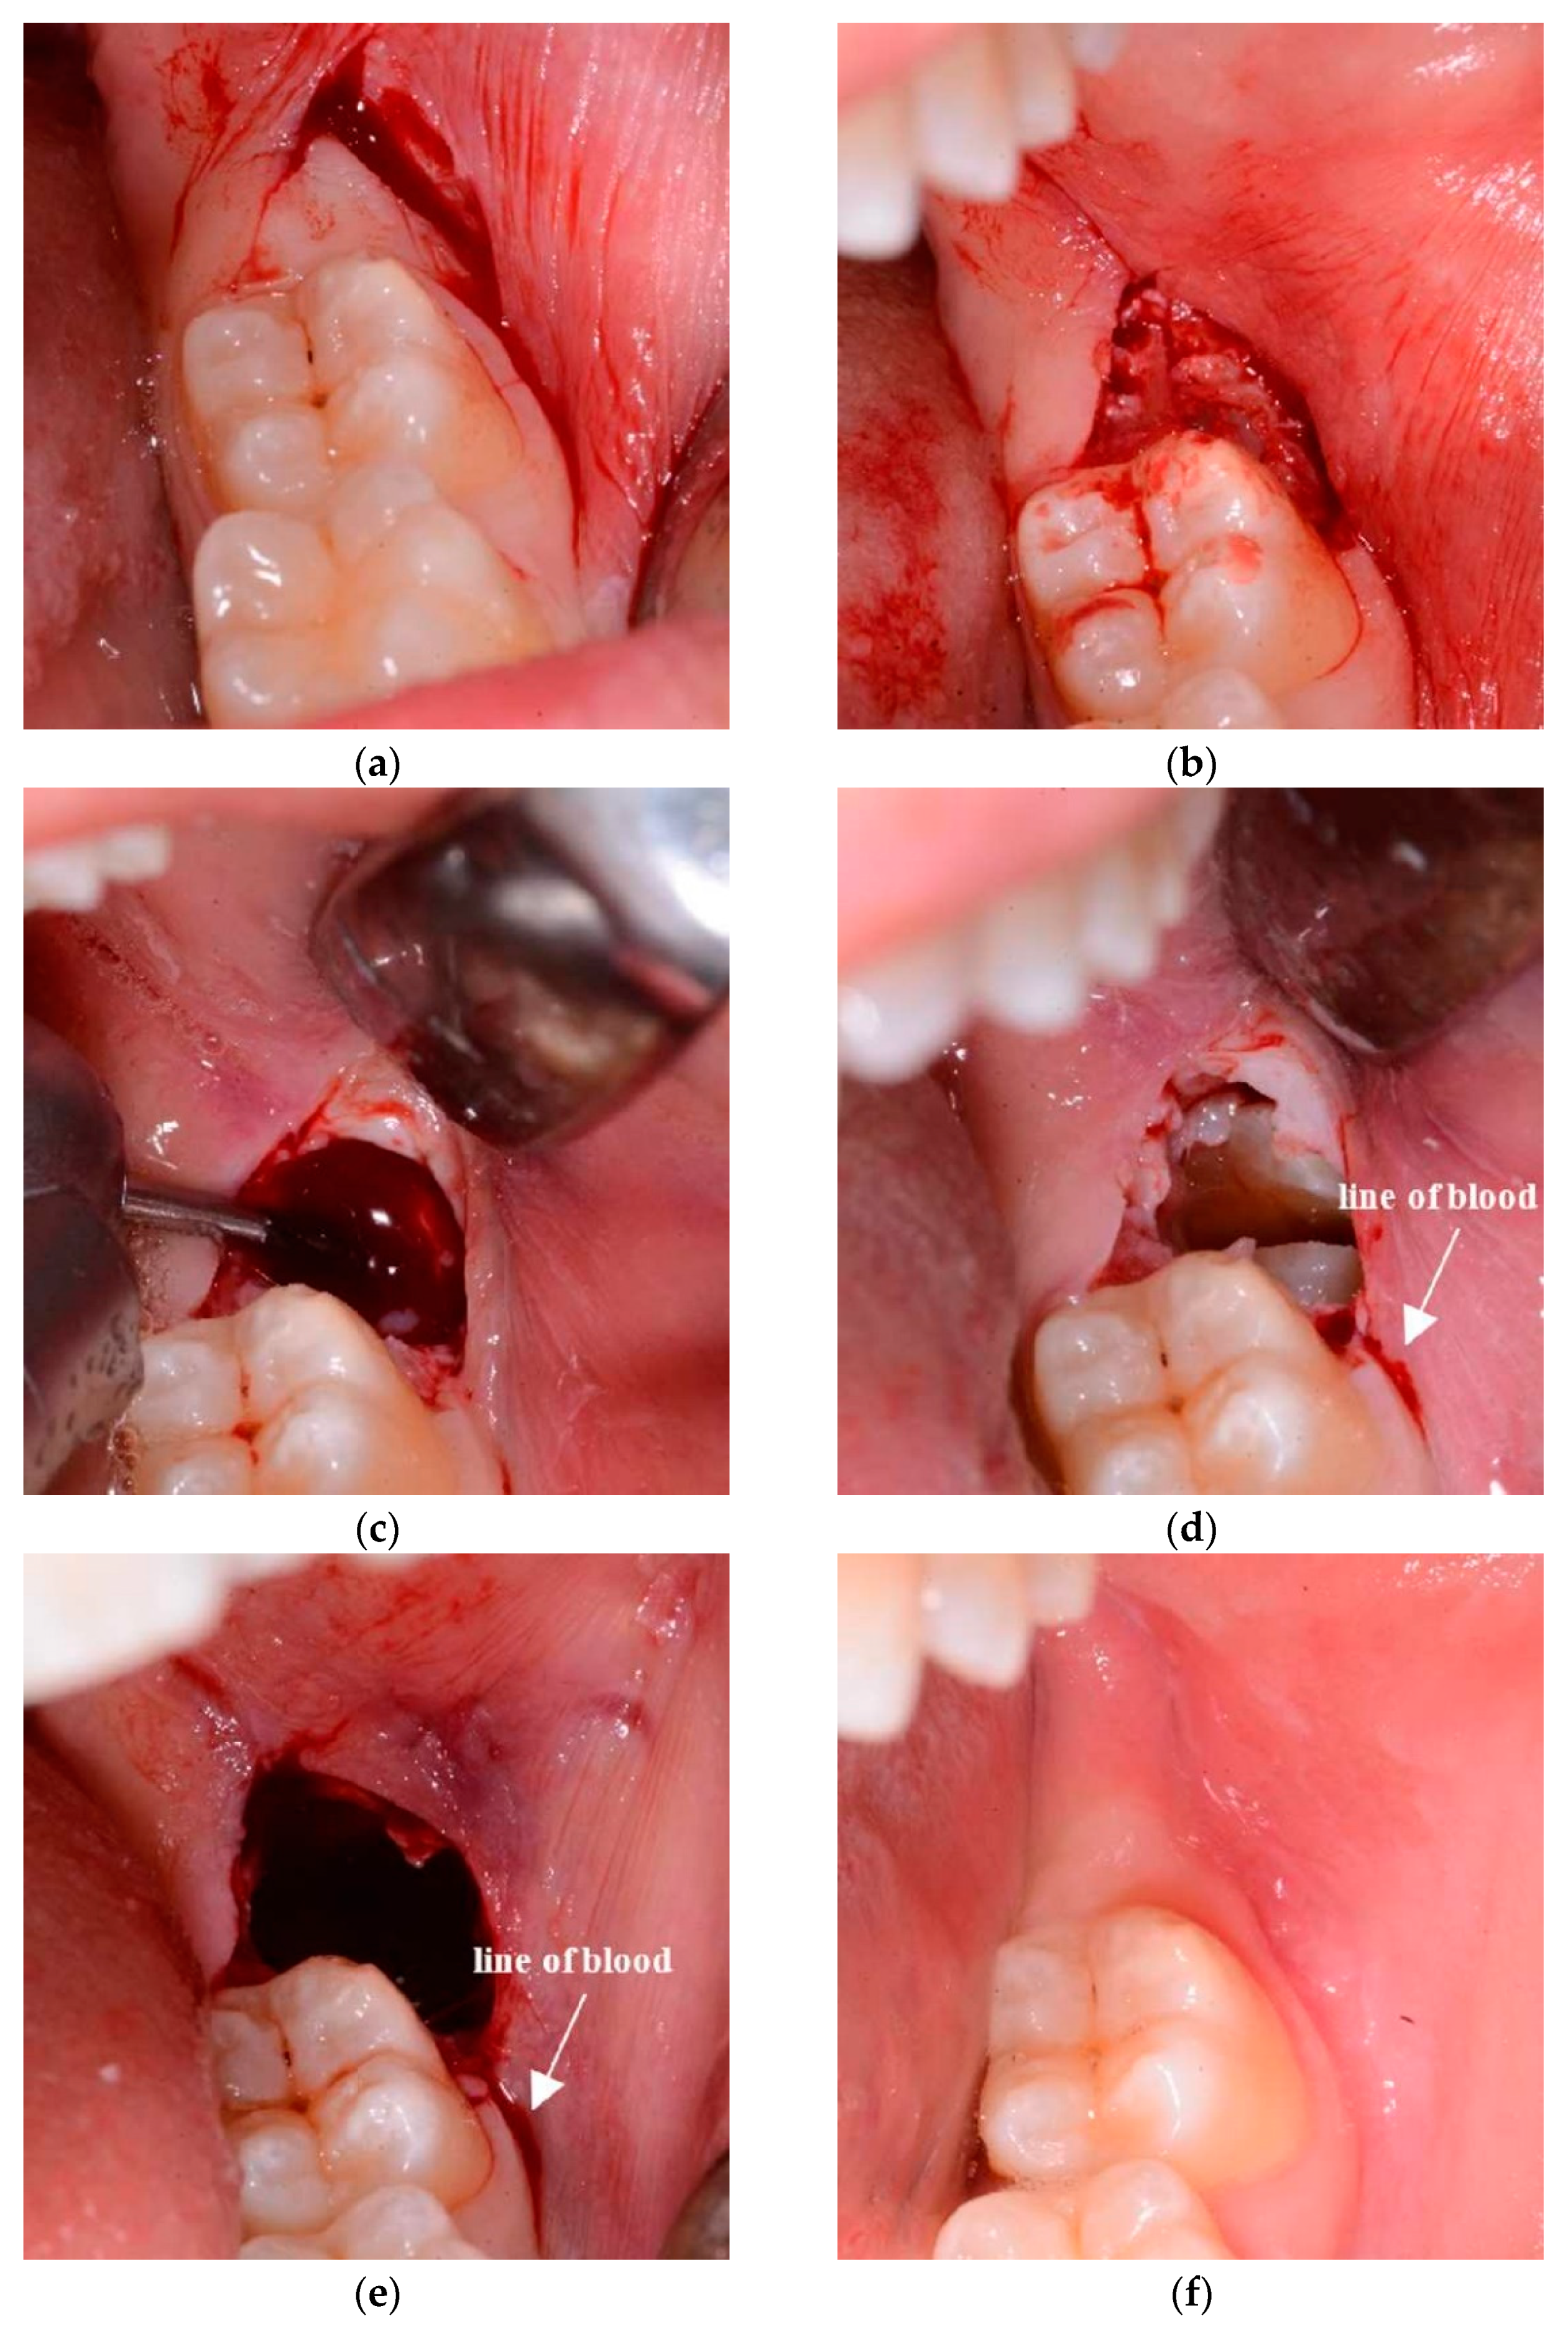

Figure 2.

Images of the surgery with the flapless surgical approach (a–e) and wound healing of post-operative recovery (f). (a) Area of soft tissue delimited by 2 incisions; (b) partial thickness tissue area removed; (c) ostectomy; (d) odontotomy; (e) end of the surgery: the wound heals through an open follow-up core, so sutures are absent. (f) At 8 weeks, the wound is healed and the soft tissue physiologically recovered.

Flapless surgical approach (FSA): consists of a first distal incision equal to that on the control side (TA). The incision begins from the distal surface of the 2M in the attached gingiva, moving the 15c Swann-Morton blade distobuccally 45° (Swann-Morton Limited Owlerton Green, Sheffield, UK) for around 10 mm. The starting point must be in the attached gingiva to avoid lingual nerve damage. Therefore, the beginning of the incision can be at the distolingual cusp of the 2M or shifted to the distobuccal cusp in case of the absence of attached gingiva in that area. The second incision begins at the distal end of the first incision and describes approximately the form and position of the probable ostectomy, which has to be performed against the buccal surface of the impacted wisdom crown. The blade describes herewith a semicircle in the buccal mucosa, ending against the buccal surface of the 2M in correspondence of the enamel sulcus, which divides the two buccal cuspids (Figure 1c and Figure 2a). The area of soft tissue is now delimited from the two incisions and the surface of the M2. The mucosa distal to the M2 is removed (Figure 1d and Figure 2b) with the help of a mini-Friedmann 90° rongeur, so a kind of partial-thickness flap is realized just above the impacted M3.

In both cases, a buccal ostectomy is performed using a surgical steel bur (Komet H31LR316 016, Komet Dental Gebr. Brasseler GmbH & Co., Lemgo, Germany) in a 45° angle surgical handpiece with cooling water port and no air spray (NSK TI-MAX 45° Stand-Titan, NSK Dental, Kanuma, Japan) (Figure 2c). The use of a traditional air-driven motor to ablate soft tissue is not recommended, because its features might cause tissue emphysema. Additionally, the only soft tissue of the buccal side has to be removed to avoid lingual nerve damage. Basically, the only difference between the two sides is that, on the test side, the bur cuts not only the bone but also the overlying partial-thickness soft tissues, such as the periosteum and part of the remaining connective tissue.

An odontotomy (Figure 2d) is then performed in order to be able to extract the tooth more efficiently through the use of surgical steel bur (Komet H31LR316 016, Komet Dental Gebr. Brasseler GmbH & Co., Lemgo, Germany) in a 45° angle surgical handpiece with cooling water port and no air spray (NSK TI-MAX 45° Stand-Titan, NSK Dental, Kanuma, Japan).

The side treated with the FSA ends without suture (Figure 2e) because no flap has been elevated and no soft tissue has free mobility. The alveolus on the test side surgery is left to heal naturally without external help, just like a normal post-extraction socket of an erupted tooth. Every patient was discharged after being instructed with the post-surgical indications as follows: (1) ice in contact with the cheek, alternating the side every 5 min all day long (2) only cold food for the first day and no rinsing for the first day, (3) take the prescribed ibuprofen 600 mg, 1/12 h–3 days (Ibuprofen Sandoz, Sandoz-Novartis, Holzkirchen, Germany), (4) mouth rinse with 0.12% chlorhexidine from the day after surgery, after eating, for the whole week. No antibiotic therapy was administered, according to previously used protocols [17,18,19].